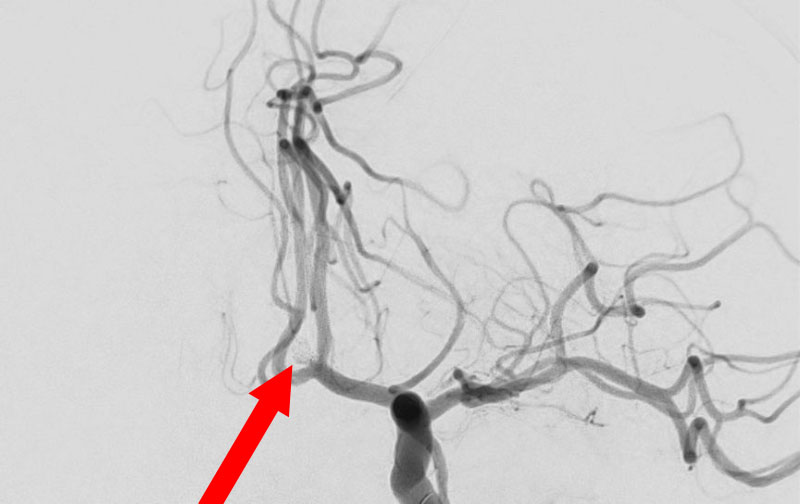

'26年4月

左椎骨動脈後下小脳動脈分岐部動脈瘤

70代

院内外来

No.1628 手術前

No.1628 手術中

No.1628 手術後